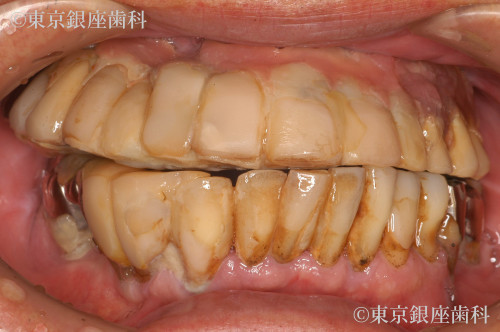

Before

After

昔行ったインプラントからワンデイインプラントに変更

歯周病が進行したため、上下でワンデイインプラントを実施